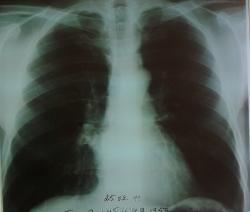

Мужчина лет 50-ти.Жалобы на кашель с мокротой, субфебрильную температуру.Пока лечим пневмонию.

А по-существу тень не очень красивая. На прямой я ее не вижу, может потому что снимок переэкспонированный.

Уважаемый коллега!На прямой тень прилежит практически к корню.Боковые снимки делались в один день( сегодня).Прямой тоже.Первичные снимки от 22.02.2011 сделаны цифровым флюорографом-без динамики.По мне тоже тень не особо привлекательна.

Не рискну трактовать такие снимки - кроме подозрения на расширение правого корня, ничего толком не видно, к сожалению.  Согласна с 1-м постом, контроль после противовоспалительного лечения.

Прямой снимок, конечно, переэкспонирован, боковой ( фотограф из меня никудышный, хотя следовала советам коллег)получился не очень, но, если его не увеличивать, то "тенюшку"на фоне сердечной тени видать хорошо.